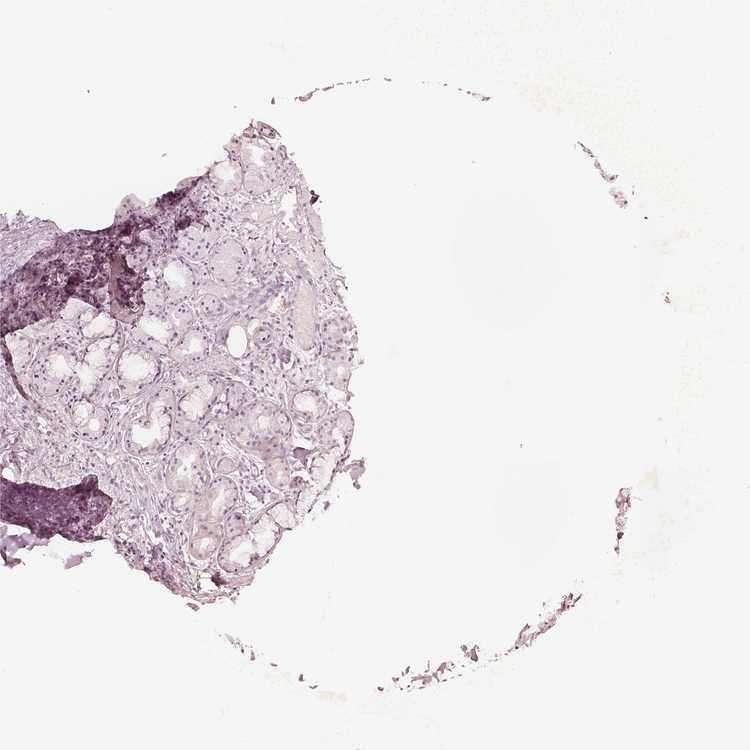

SOFT TISSUE 2 - Antibody stainingi

Antibody staining in the annotated cell types in the current human tissue is reported as not detected, low, medium, or high, based on conventional immunohistochemistry profiling in selected tissues. This score is based on the combination of the staining intensity and fraction of stained cells.

Each image is clickable and will lead to virtual microscopy that enables deeper exploration of all samples and also displays staining intensity scores, fraction scores and subcellular localization as well as patient and tissue information for each sample.

Antibody HPA061969

Fibroblasts Not detected

Peripheral nerve Not detected